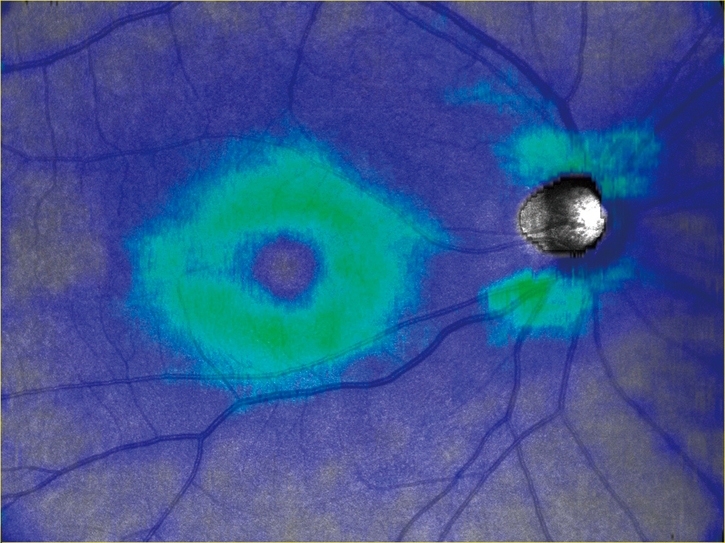

任意設定により5種類(初期設定:網膜全層、表層、深層、外層、脈絡膜)のパノラマが同時に自動合成できます。

網膜全層 HD4 4.5×4.5mm 6枚 パノラマ |

網膜表層 |

網膜深層 |

網膜外層 |

脈絡膜 |